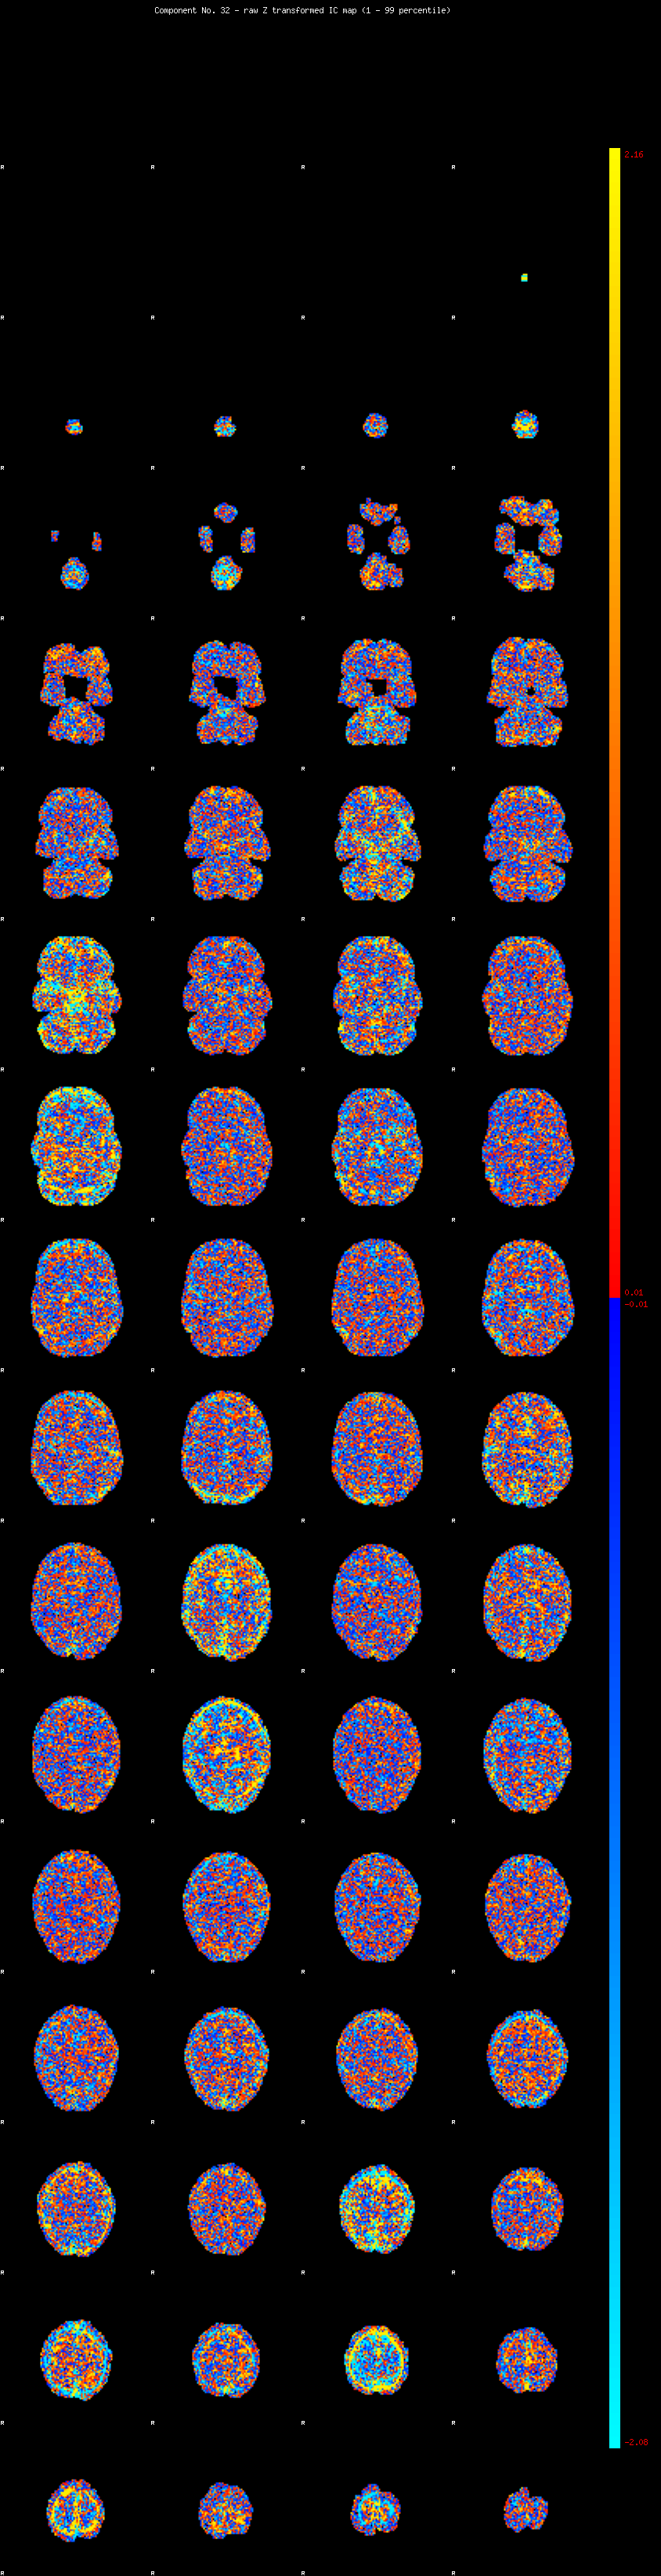

IC_32 Mixture Model fit

Means : 0.000000 3.009961 -2.574655

Vars : 1.000000 3.973511 2.309877

Prop. : 0.917670 0.040864 0.041466